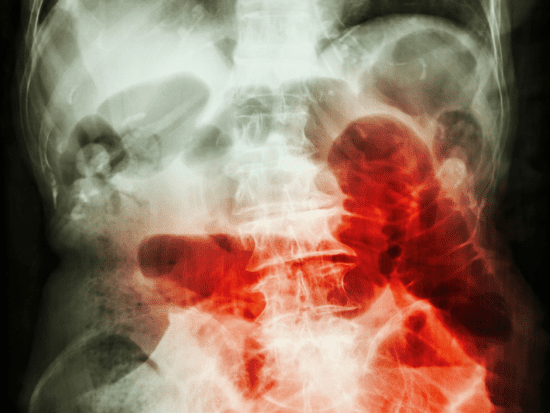

Intestinal obstruction is a blockage that keeps food or liquid from passing through your small intestine or large intestine.

At the specific place where my intestine was reconnected after the ileostomy was removed, there is a band of adhesion now, clearly visible on the CT, every time I get my bowel obstruction.